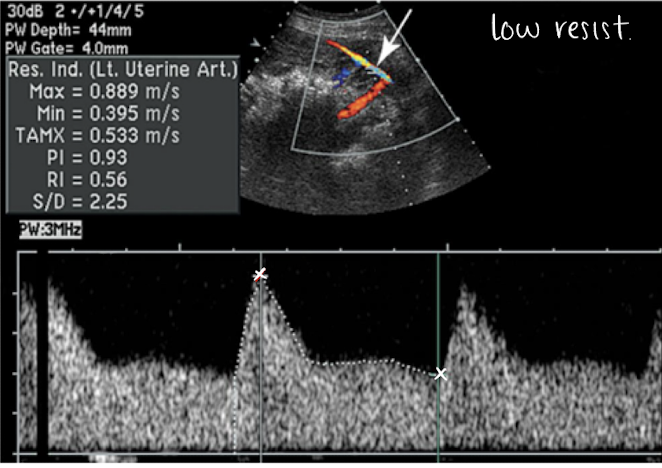

placental PW doppler and SONO evaluation

uterine artery PW (varies based on trimester):

high RI flow pattern in 1st trimester

low RI flow pattern in 2nd trimester

lots of blood flow going through uterine artery to get to placenta and supply baby with oxygen

SONO evaluation:

use optimal gate, gain, scale, placement

measure waveform and RI